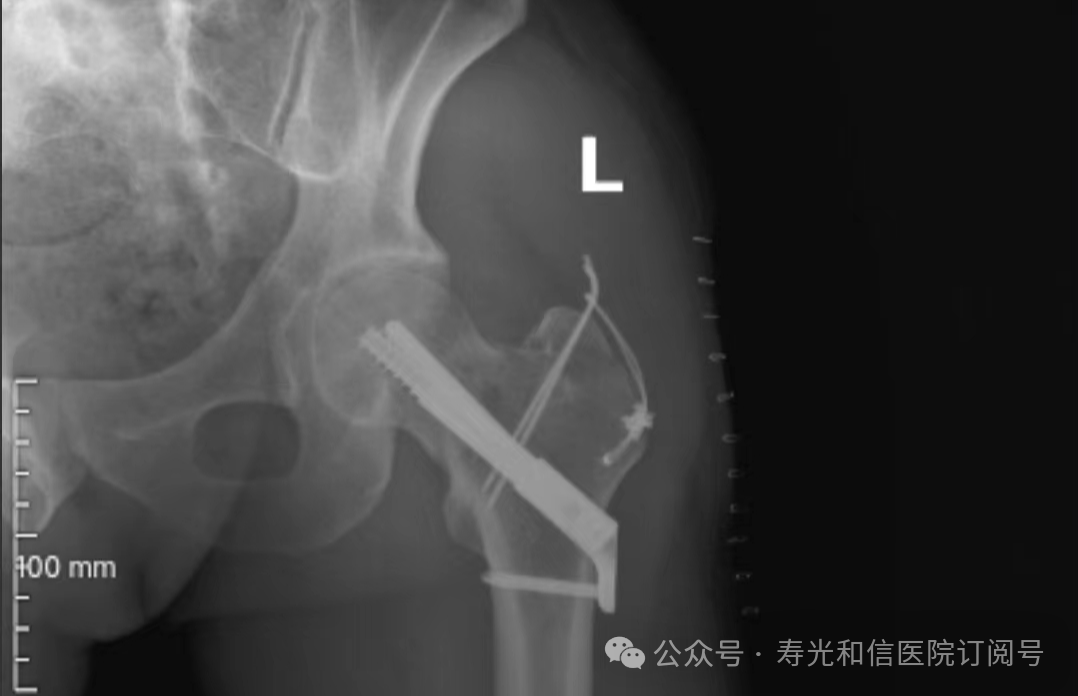

患者经120接诊,完善相关辅助检查后收入寿光和信医院骨外科。检查发现,患者右锁骨骨折、左股骨颈骨折、左大转子撕脱骨折、右膝关节前交叉韧带止点撕脱骨折、右膝关节外侧副韧带损伤、颅骨骨折及全身多处皮肤挫伤。因患者是外地来寿人员,家属短时间内不能赶过来,并且患者家庭经济条件较差,没有缴纳住院手术费的能力。但是股骨颈骨折后,股骨头坏死发生几率较高,手术越早进行,越有利于减少发生股骨头坏死的几率。骨外科主任李刚始终牢记救死扶伤的神圣职责,本着为病人负责的原则,坚定地选择先行为患者实行手术治疗。

与患者本人充分沟通后,李刚主任率领骨外科团队,经过充分的术前讨论及术前准备,于2024年9月1日为患者在全身麻醉下实施了4个半小时的内固定手术治疗。“时间就是生命”,手术过程中,全体参与人员密切观察病情变化,敏锐发现早期异常指标,争分夺秒,一丝不苟地做好各项抢救救治工作,做到瞬间判断、正确评估、果断处理,赢得了抢救患者的“黄金时机”,确保了手术的顺利完成。

在为其进行股骨颈骨折治疗时,手术团队为其采取了股骨颈动力交叉钉系统,这是一种新型股骨颈内固定系统,属微创植入,较从前的技术具有手术时间短、创伤小、力学稳定、滑动加压等优点。同时,患者恢复快,可早期离床、不负重下活动,缩短住院时间及康复时间,有效降低患者股骨颈骨折不愈合发生率,降低长期卧床合并症和死亡率。